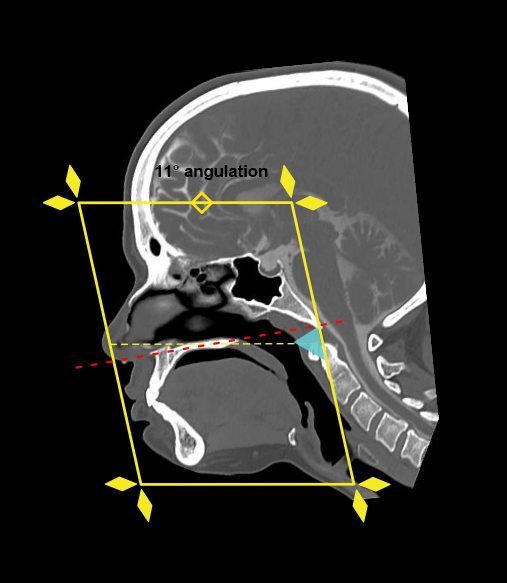

- In prone method (neck hyperextended), plan the scan slab to cover from nose to posterior margin of sphenoid sinus. Scan slab needs to be perpendicular to hard palate, which is achieved by tilting the gantry.

- Reducing the FOV to sinus area increases image quality [7].

Explanation: this increases geometric resolution.